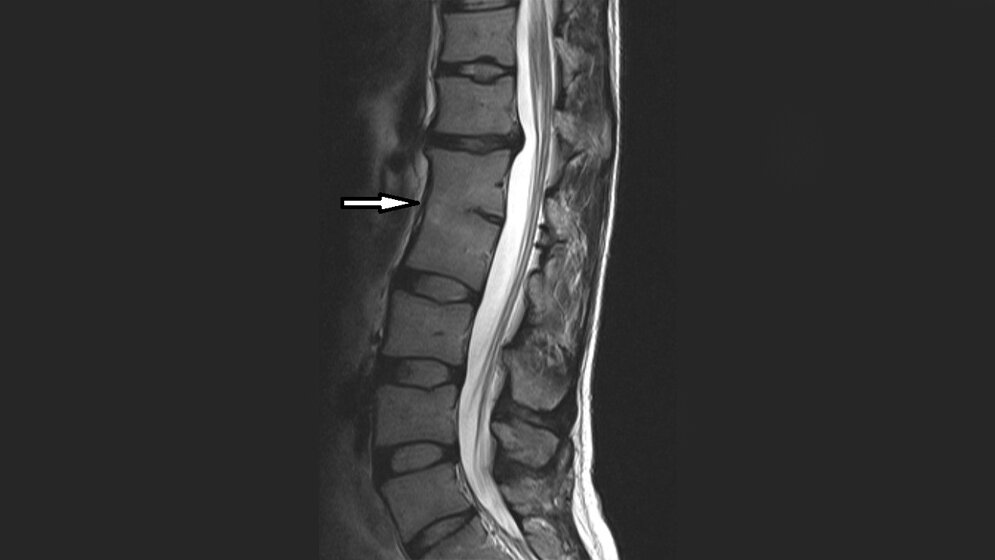

Angeborene Wirbelsynostosen können eine klinische Bedeutung haben. Die Kenntnis der Veränderungen ist wichtig, da sie mit neurologischen Symptomen einhergehen können. Insbesondere ist das Risiko der zervikalen Myelopathie bei Patienten mit Blockwirbeln der Halswirbelsäule höher.

Spine synostosis as embryological basis can‘t or can have clinical implications. To know the details is clinically important as they might be associated with neurological signs and symptoms. The prevalence of cervical myelopathy in congenital cervical spine fusion is higher than for the general population.